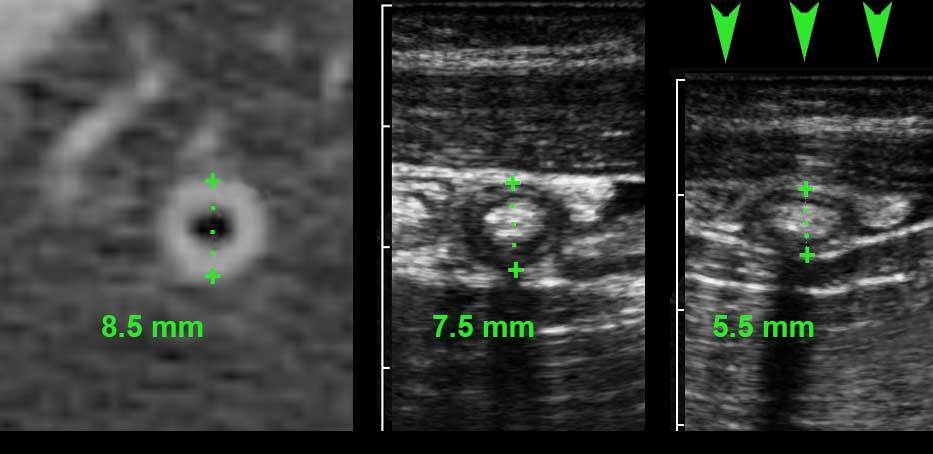

Đo lường trên CT đánh giá cao hơn đường kính ruột thừa so với siêu âm.

Trong y văn, đường kính trung bình trên CT của ruột thừa bình thường là 6,5-8 mm (dao động từ 3 đến 14 mm).

The explanation for this discrepancy may be that on CT:

- The serosa is included in the measurement

- There is no compression involved.

- Ngoài ra, đường viền của ruột thừa trên CT khá mờ, khiến các phép đo kém tái lập hơn.

Hình bên trái cho thấy hình ảnh CT của ruột thừa bình thường chứa đầy phân với đường kính 8,5 mm.

Hình ảnh ở bảng giữa là siêu âm của một ruột thừa bình thường tương đương ở một bệnh nhân khác với kích thước 7,5 mm, bảng bên phải cho thấy ruột thừa đó trong quá trình ép (5,5 mm).

Tài liệu y văn chỉ ra rằng đường kính siêu âm của ruột thừa bình thường là 6 mm hoặc nhỏ hơn trong 73% các trường hợp.